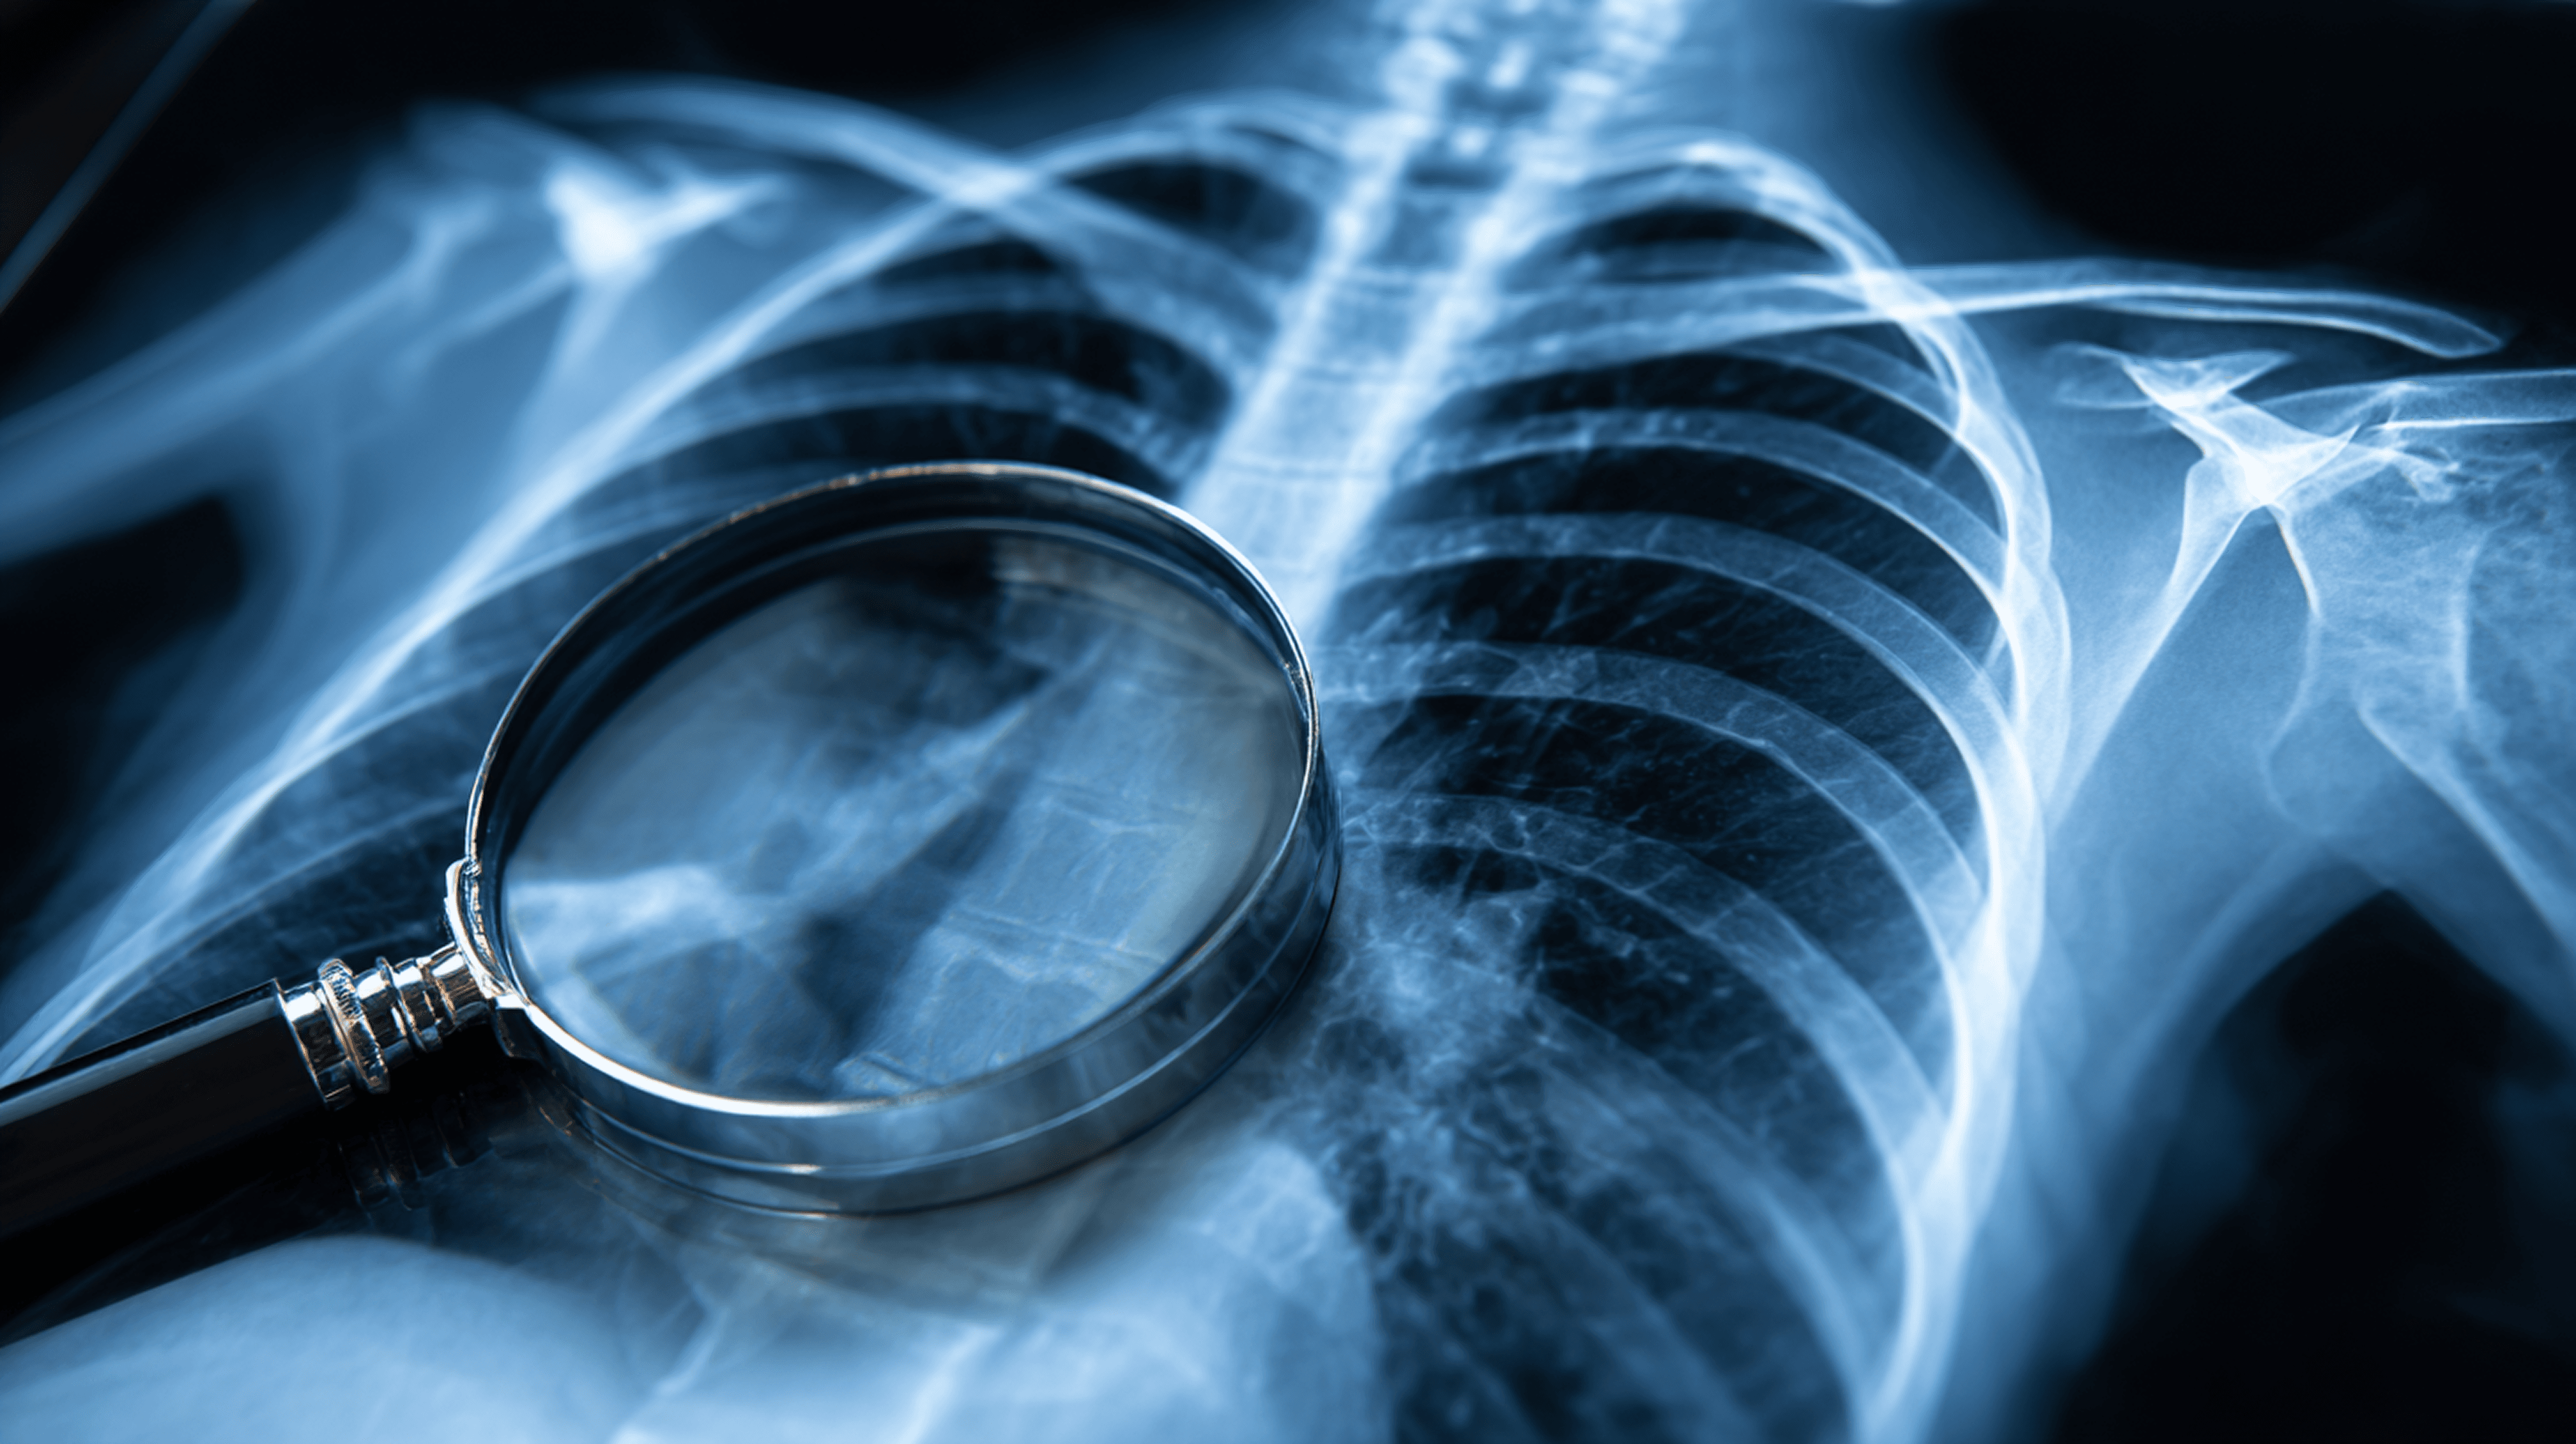

흉부 X-ray는 흔히 ‘폐를 보기 위한 검사’라고 생각합니다. 폐렴, 결핵, 심장비대, 기흉 등을 확인하는 데 가장 기본이 되는 검사이기 때문이죠. 하지만 이 영상에는 우리가 미처 보지 못했던 또 하나의 중요한 정보가 숨어 있습니다. 바로 뼈의 상태, 특히 골소실(bone loss)의 초기 신호입니다.

그동안 이 정보는 판독 과정에서 ‘배경(background)’ 취급을 받았습니다. 그러나 최근에는 프로메디우스가 개발한 흉부 X-ray 기반 골다공증 선별 AI 기술술이 이 영역에서 새로운 가능성을 열고 있습니다.

사실 X-ray는 뼈를 가장 잘 보여주는 영상입니다. 방사선은 단단한 물질을 통과하지 못해, 뼈가 흰색으로 뚜렷하게 나타나기 때문이죠. 그럼에도 불구하고 흉부 X-ray에서 보이는 여러 뼈는 오랫동안 주변부로 취급되어 왔습니다.

X-ray에는 정보가 있었지만, 인간은 그것을 활용하지 못했다고 볼 수 있습니다.

100년 동안 우리는 X-ray에서 폐만 보았습니다. 하지만 영상 속 뼈는 늘 우리에게 신호를 보내고 있었습니다. 단지 우리가 그 신호를 읽지 못했을 뿐입니다.

프로메디우스의 골다공증 선별 AI는 그 신호를 읽어내고, 해석하고, 의미 있는 임상 정보로 바꾸는 기술입니다. 폐 영상 검사가 동시에 골다공증 조기 발견의 기회가 되는 시대가 열린 것입니다.

흉부 X-ray는 가장 오래된 영상 기술이지만, AI를 만나 새로운 역할을 갖게 되었습니다. 이제 X-ray는 폐를 보고, 심장을 보고, 뼈의 미래 위험까지 보는 종합적인 건강의 보고서가 되어가고 있습니다.